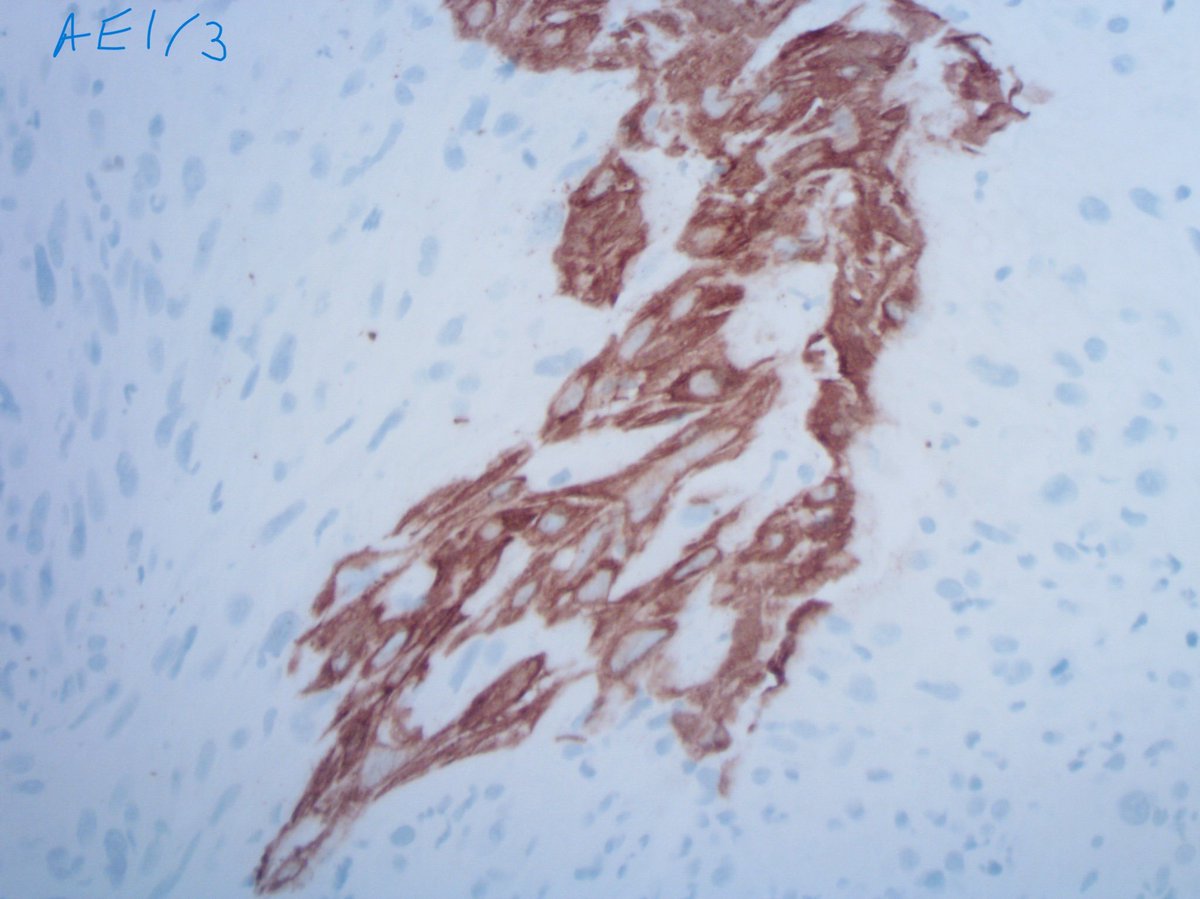

Laryngeal carcinosarcoma (sarcomatoid SCC). Sometimes you have to look v hard to find any evidence of epithelial differentiation. This was the only 1mm focus +ve for p40 and cytokeratins. Don’t believe it’s a sarcoma until you’ve done levels and every CK in your armoury #ENTPath